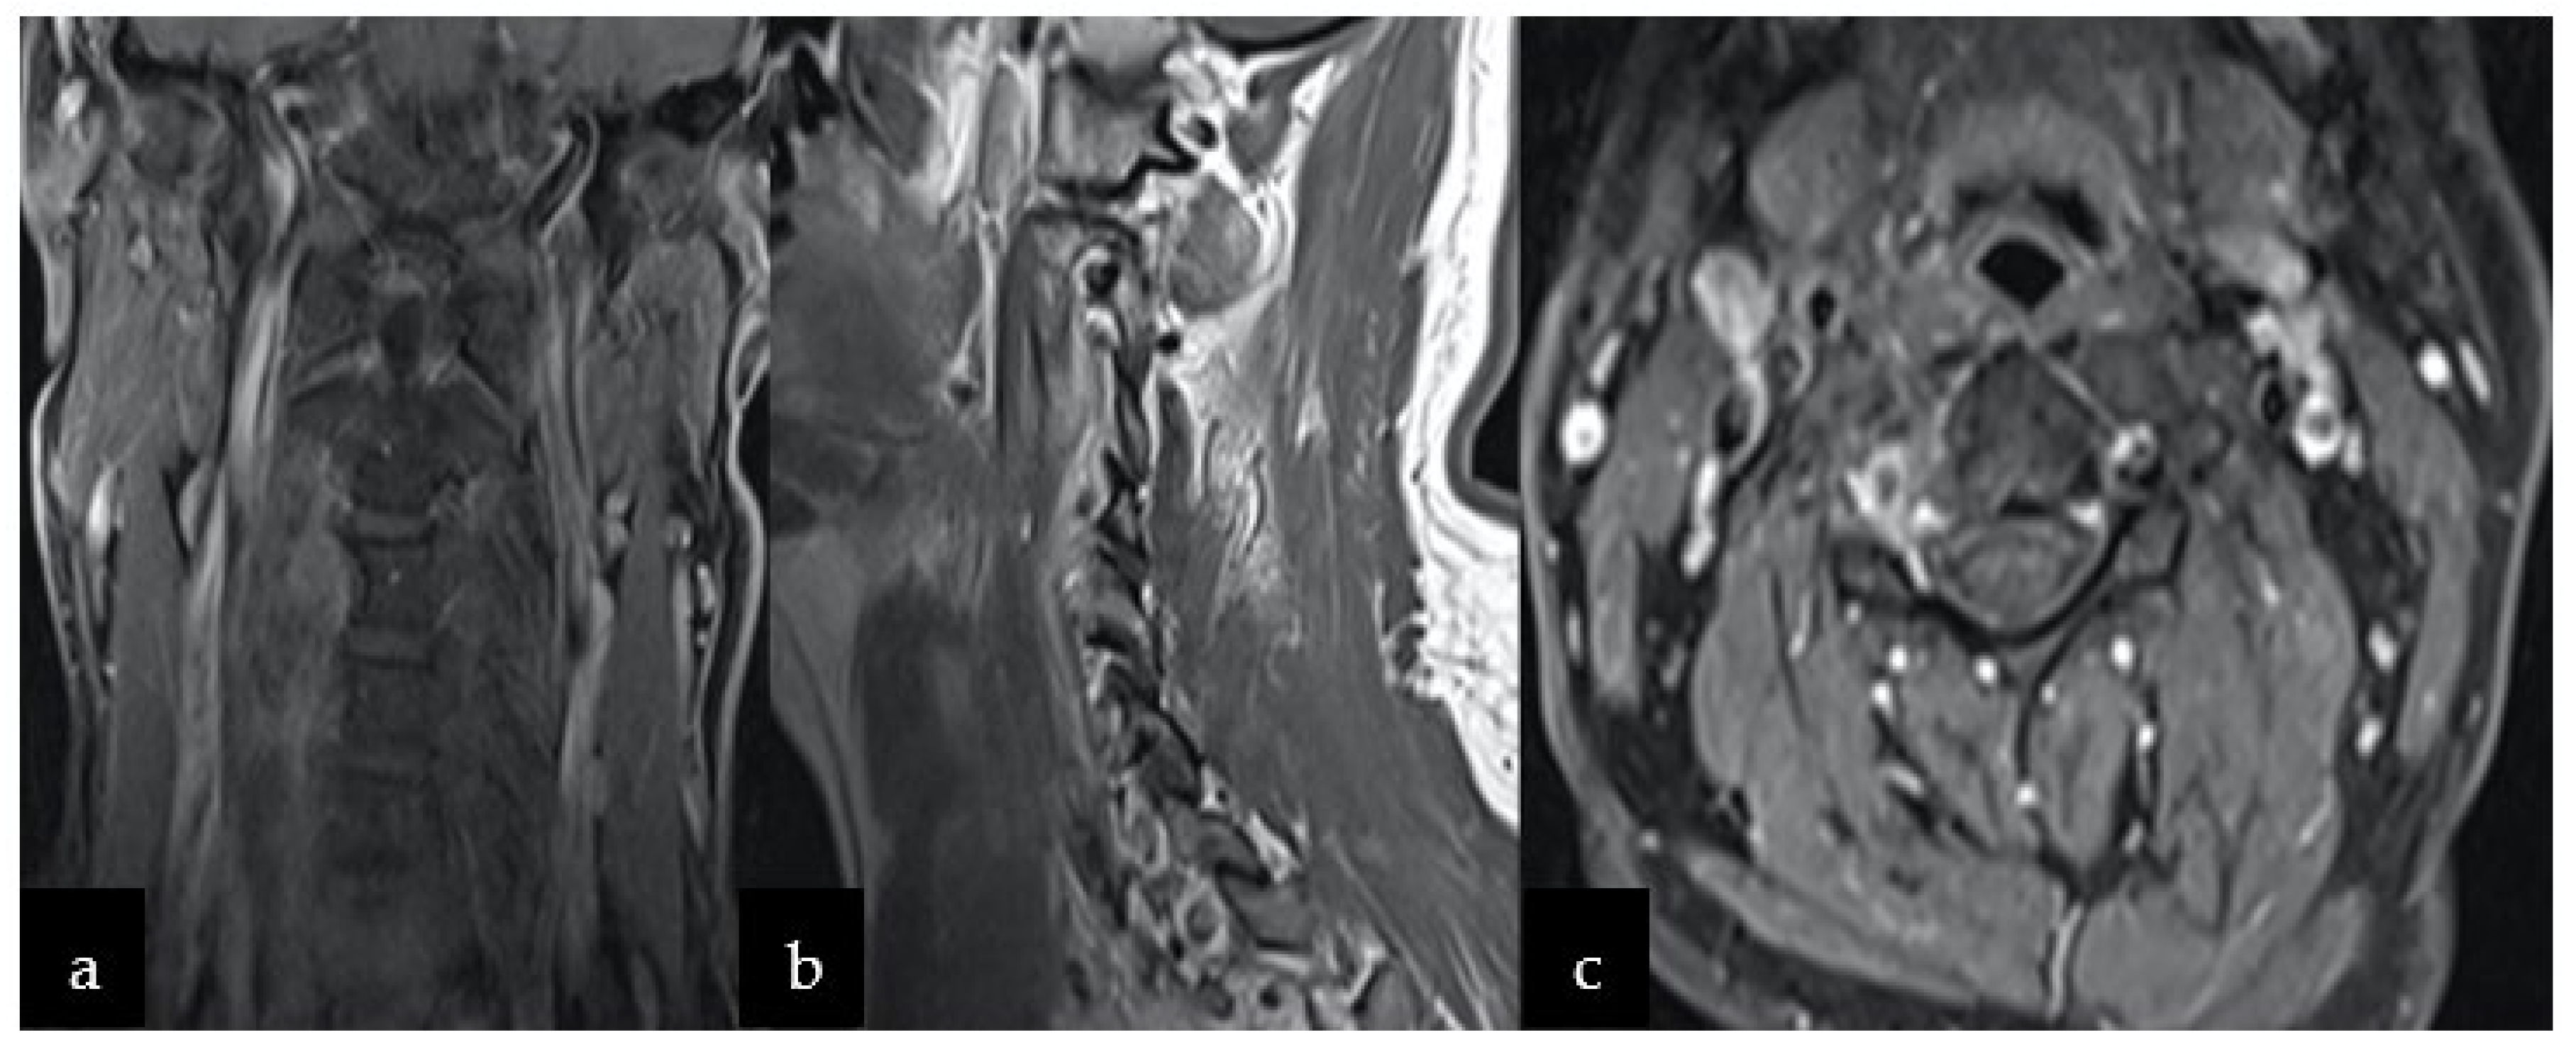

3.3. Radiological Features